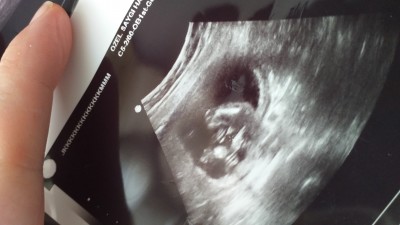

13 hafta da kiz dendi 14 haftada  erkek soyledi. 16 haftalik oldum  gecen carsamba erkek dedi pipiyi gosterdi oglun olucak dedi. Sizce degisme olasiligi var mi ?  Pipiyi gorup te ayrintili da kiz cikan var midir . Öncelik  saglikli olsun evlatlarimiz

Rabbim hayırlı olanı versin banada öyle söylendi ama sonrada %99 kız dedi eğer kesin net söylediyse sonuç degismez

20. Haftaya kadar bekle kiz sen alisveris yapma bence ayrintilida netlesir.cunku yanilma olabiliyor

Ben 19+4 de girmistim ama daha derken oluyormu bilmiyorum ama en iyisi 20. Hafta diyorlar